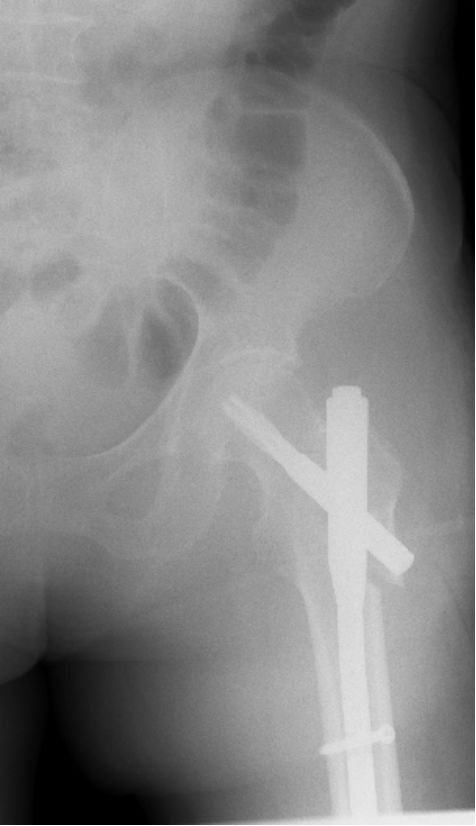

髓内固定系统:Gamma钉、PFN、PFNA、TFN 等。

PFNA(股骨近端螺旋刀片抗旋髓内钉proximal femoral nail anti-rotation blade)

新改进的PFN(股骨近端髓内钉)系统,一方面继承了原PFN 的优点,生物力学特点相同,另一方面在具体设计上有所创新,令固定更有效、操作更简单。

刀片具有宽大的表面积和逐渐增加的芯直径(4.5-9mm),通过打入,填压松质骨,可提高其锚合力,尤其适合骨质疏松患者。

与骨质贴合紧密,增强了稳定性,抗旋转、抗骨折端塌陷和内翻畸形的能力很强。

适用于几乎所有的转子间骨折,特别适合于不稳定型骨折(如反转子间骨折)及合并骨质疏松者。